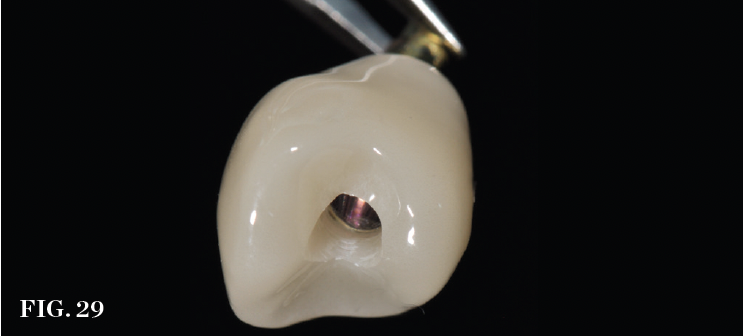

The emergence contour of a transmucosal provisional restoration must be carefully designed chairside by the clinician (Figure 28) or prefabricated by a technician (Figure 29) to support and define the marginal gingival contour, which is referred to as the critical contour, while minimizing the space occupied by the material closer to the implant-abutment interface, which is referred to as the subcritical contour. These zones of prosthetic contour will affect the facial gingival level and zenith as well as the color of the soft tissue by masking the prosthetic components.38 Undercontoured subcritical contours effectively increase the space for native soft-tissue infill, which further protects the bone at the implant collar and potentially reduces post-restoration tissue changes.39 Although provisional restorations can be fabricated chairside after surgery, prefabricating provisional crowns or custom healing abutments/bonded restorations based on the digital plan offers day-of-surgery provisionalization with esthetic and durable materials that requires less chair time because intraoperative steps are not needed to fabricate the restorative components.

(29.) Provisional crown prefabricated using a digital workflow. A nonengaging base allows freedom of rotation to accommodate minor vertical timing problems. Full contour is established in the first 1 mm subgingival to fully support the marginal gingiva, and the remaining subgingival form is undercontoured.

Figure 29